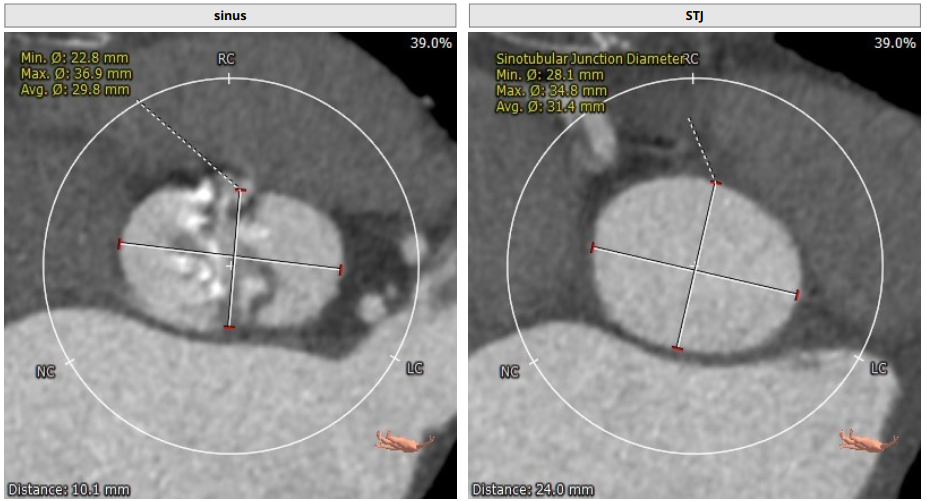

Tepy1型二叶瓣,中度钙化,瓣环直径25.6mm,LVOT32.5mm,窦部短轴最窄处22.8mm,综合考虑DOWNSIZE选择L26或者L29瓣膜。冠脉高度尚可,STJ较高,以及二叶瓣均可降低冠脉风险,整体评估冠脉风险较小,决定术中使用22mm球囊预扩确认冠脉风险及瓣膜选择。